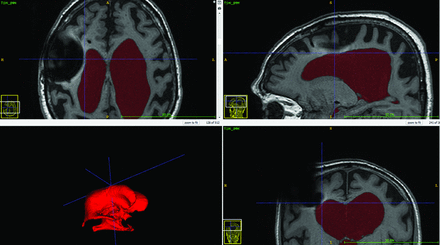

Susceptibility artifacts from metal components of the shunt valve can potentially reach into the lateral ventricle ipsilateral to the site of shunt placement and disturb the VV measurement on the postoperative MR imaging scans. We observed these susceptibility artifacts present in 3 patients, but in all of these patients, the contour of the wall of the lateral ventricle was clearly visible. Figure 4 shows postoperative MR imaging in 1 patient, in which susceptibility artifacts from the shunt valve extended into the right lateral ventricle without affecting the contour of the wall of the lateral ventricle. Therefore, we believe that the susceptibility artifacts did not affect the volumetric measurements in the present study. However, we found the presence of the susceptibility artifacts on postoperative MR imaging scans to be a limiting factor for measurement of total intracranial volumes; therefore, this measure was not assessed in this study.

Ventricle volume segmentation in the ITK-SNAP software showing how susceptibility artifacts from the shunt valve appeared on the postoperative MR imaging.